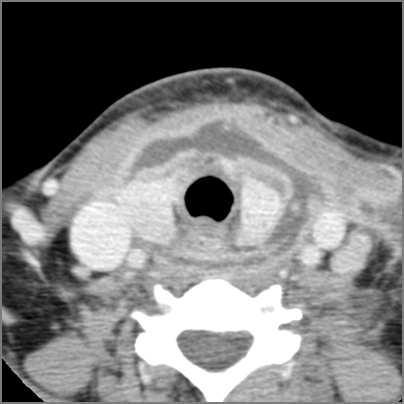

Hypopharynx, Larynx, Deep Neck and Entire Retropharyngeal Space

There is excessive enhancement or thickening of the mucosa within in the hypopharynx, larynx or trachea. [Yes/No]

There is edema within in the hypopharynx, larynx or trachea. [Yes/No]

There is abscess within in the hypopharynx, larynx or trachea. [Yes/No]

There is edema within the adjacent deep neck, retropharyngeal and/or prevertebral spaces [Yes/No]

There is abscess within the adjacent deep neck, retropharyngeal and/or prevertebral spaces. [Yes/No]